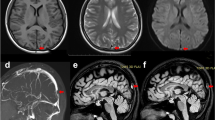

Imaging data

Brain magnetic resonance imaging (MRI) displayed diffuse T2-weighted fluid-attenuated inversion recovery (FLAIR) and diffusion-weighted imaging (DWI) white matter hyperintensities in bilateral corona radiata areas (Fig. 1A-B). The susceptibility-weighted imaging (SWI) and magnetic resonance venogram (MRV) of the brain showed extensive tortuous dilatation of the intracranial veins (Fig. 1C-D).

Brain MRI scan. T2-weighted FLAIR (A) and DWI (B) sequences of brain MRI scans reveal abnormal white matter signals in bilateral corona radiata areas. SWI (C) and MRV (D) sequences of brain MRI scans reveal extensive tortuous dilatation of intracranial veins. After DAVF embolization, T2-weighted FLAIR (E) and DWI (F) brain MRI scans show improvement in white matter lesions. SWI (G) and MRV (H) sequences of brain MRI show a significant reduction in multiple vascular shadows on the brain surface and subcortex. Abbreviations: MRI = magnetic resonance imaging; FLAIR = fluid attenuation inversion recovery; DWI = diffusion-weighted imaging; SWI = susceptibility-weighted imaging; MRV = magnetic resonance venography; DAVF = dural arteriovenous fistula

Shortly after admission, the diagnoses of CVST and DAVFs were made, and the patient received oral anticoagulation treatment with rivaroxaban. Subsequently, DAVF embolization (Fig. 2E-F) and balloon dilation of the left transverse sinus (Fig. 2G) were performed. Ten days after the surgery, a brain MRI showed that white matter hyperintensity decreased on T2-weighted FLAIR and DWI sequences (Fig. 1E-F). SWI and MRV imaging showed a significant reduction in multiple vascular shadows on the brain surface and subcortex (Fig. 1G-H).